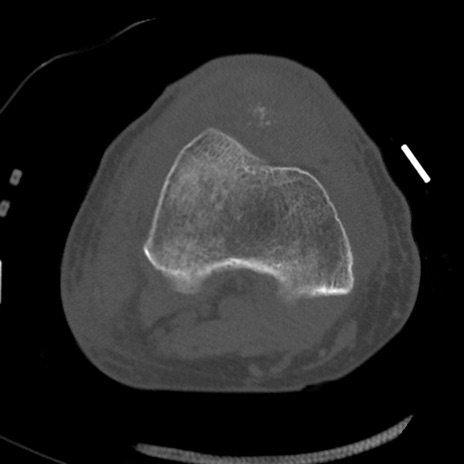

症例28 右膝関節CT(横断像)

右膝関節CT